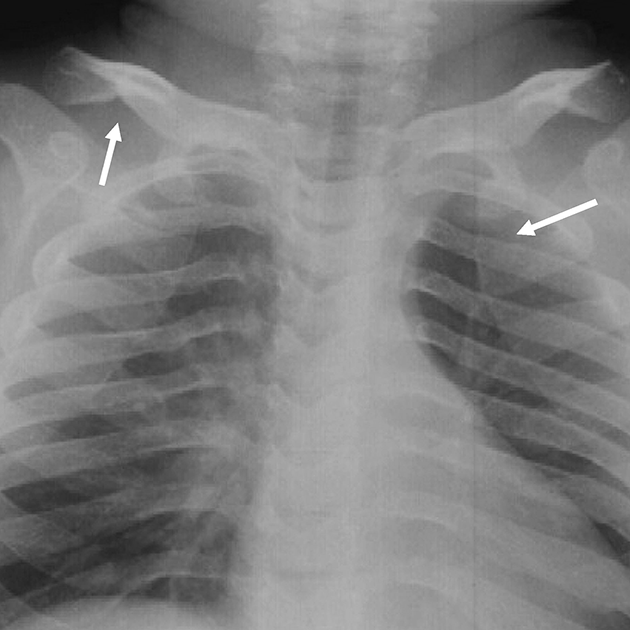

Radiografía de tórax anteroposterior en una paciente de 11 años con MPS VI donde se observan costillas gruesas pero no con forma de pala y clavículas gruesas.

Fuente: Skeletal Radiology, volume 43, issue 3. Lachman RS, Burton BK, Clarke LA, Hoffinger S, Ikegawa S, Jin D-K, Kano H, Kim O-H, Lampe C, Mendelsohn NJ, Shediac R, Tanpaiboon P, White KK. Mucopolysaccharidosis IVA (Morquio A syndrome) and VI (Maroteaux-Lamy syndrome): under-recognized and challenging to diagnose. Pages 359-369. Copyright (C) Lachman RS, Burton BK, Clarke LA, Hoffinger S, Ikegawa S, Jin D-K, Kano H, Kim O-H, Lampe C, Mendelsohn NJ, Shediac R, Tanpaiboon P, White KK 2014.